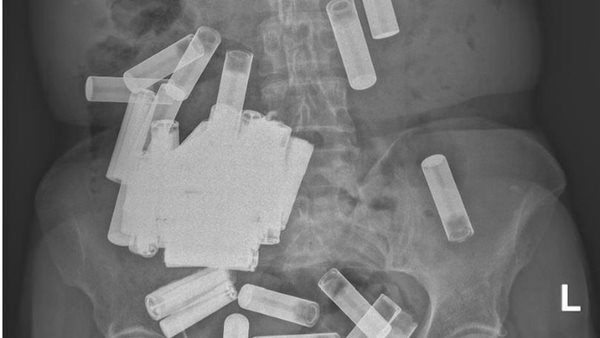

وجد الطاقم الطبي في مستشفى جامعة سانت فنسنت في دبلن 55 بطارية في جسد امرأة، تبلغ من العمر 66 عامًا، حيث رصد الباحثون البطاريات في منطقة المعدة والقولون.

اكتشف الباحثون الـ 55 بطارية في جسد المرأة بعد أن حددت الأشعة السينية أجسامًا غريبة في جسدها، ولحسن حظها، لم يكن أي منها يعيق جهازها الهضمي، لذلك كان الأطباء يأملون في أن تمر بها بشكل طبيعي، حسب موقع Live Science.

واتخذ الجراحون إجراءات وأزالوا 46 من البطاريات المتبقية، واستمر أربعة منهم محاصرين في القولون، حيث قام الأطباء بسحبهم في منطقة الشرج لإزالتها من فتحة الشرج، وبذلك يصل إجمالي عدد البطاريات التي وجدت في جسدها إلى 55 بطارية.